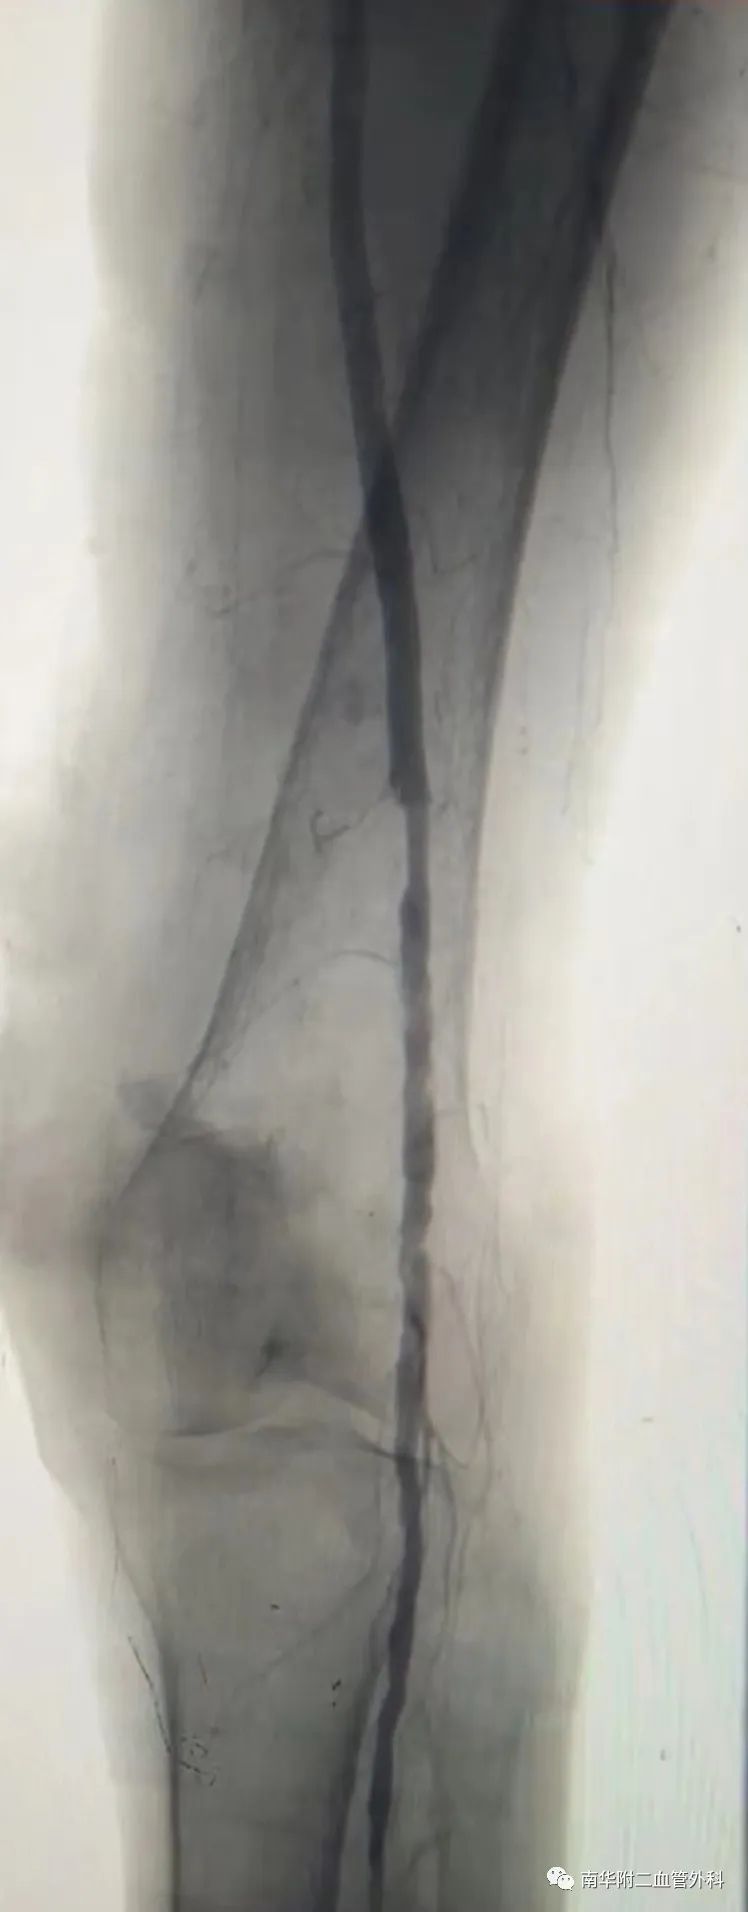

图片:术后造影效果

熊国祚教授团队为患者先行实施置管溶栓术,数日后再为患者实施经皮动脉内球囊扩张术,手术用时近三小时,顺利完成。术后,患者左侧皮温明显转暖,左下肢缺血情况得到明显改善。